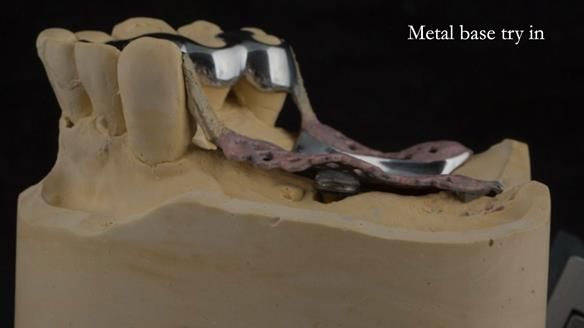

Instead, we made a Scandinavian-style, metal-based lower RPD.

A metal-based upper RPD was made,

with metal backings incorporated to future-proof the design

should further teeth fail.